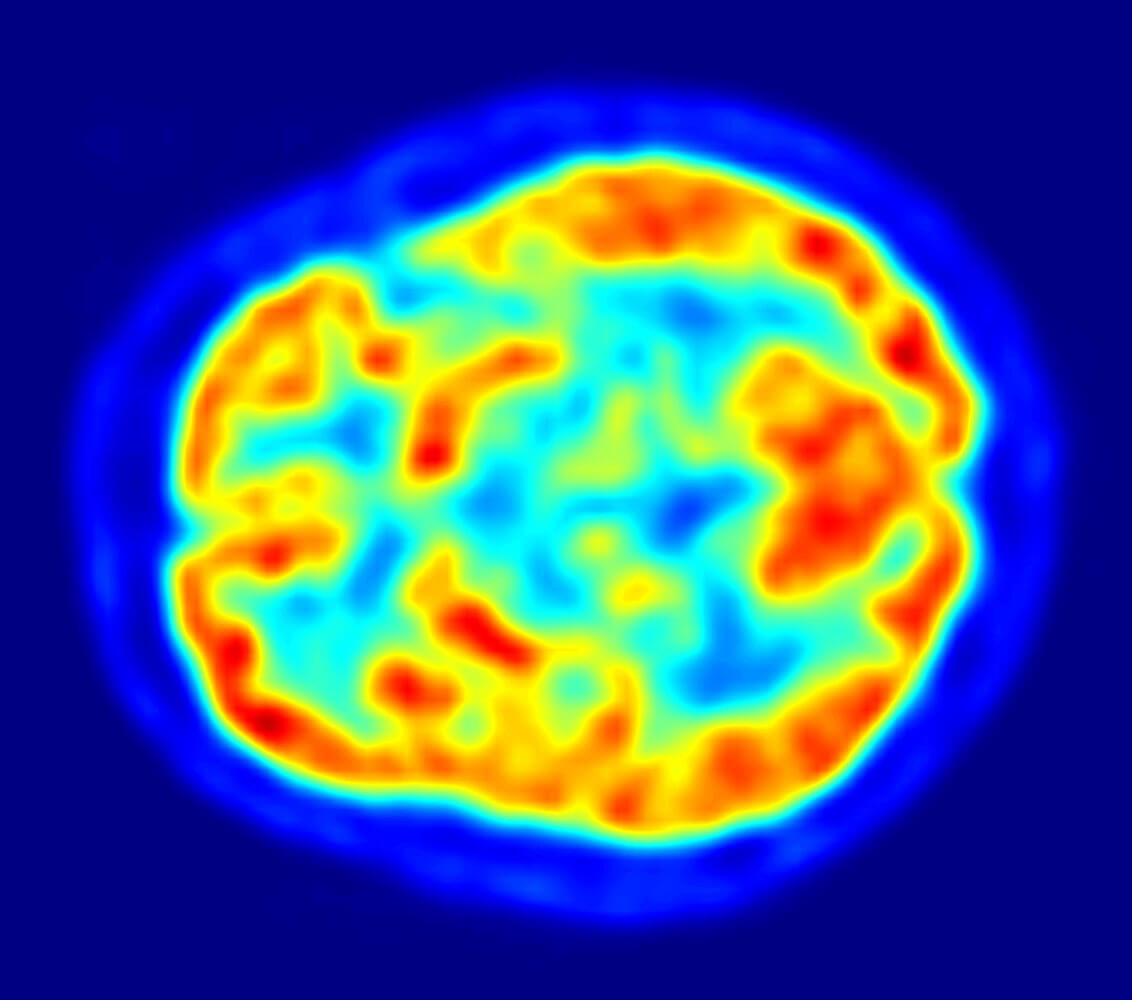

Este periodo está marcado por el surgimiento de las imágenes cerebrales como la tomografía axial computarizada (TAC), que supuso una revolución en las neurociencias.

Esto ha permitido que se obtengan correlaciones clínico-anatómicas más precisas y que muchos conceptos sean redefinidos y aclarados. Con los avances se ha podido comprobar que existen otras áreas que no son “clásicas” en la neuropsicología y que participan en procesos cognitivos.

En la década de 1990 la investigación avanza de la mano de imágenes no ya anatómicas, sino funcionales. Por ejemplo, las que se obtienen a través de la resonancia magnética funcional (RMf) y la tomografía por emisión de positrones (TEP). Estas técnicas permiten observar la actividad cerebral durante la realización de actividades cognitivas como hablar, leer, pensar en palabras, etc.

Por otro lado, la neuropsicología también se sirve de técnicas de neuroimagen modernas como las resonancias magnéticas funcionales o los electroencefalogramas, que permiten estudiar la actividad cerebral de forma directa sin tener que llevar a cabo ningún tipo de cirugía.